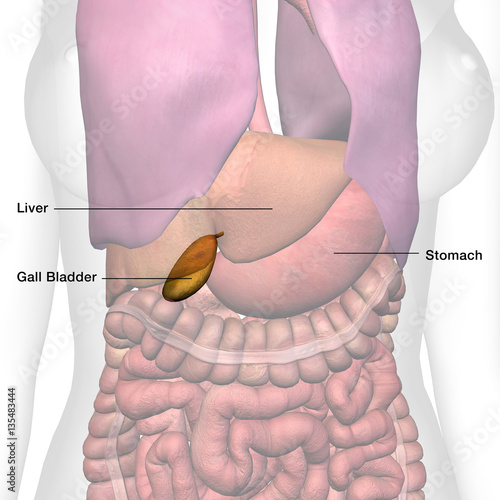

Female Gall Bladder Anatomy Labeled – Buy this stock illustration and …

Pin on Household and Recipe Tips

Pin on Health

Pin on Symptoms and Conditions

Pin on All about Health

Pin on health